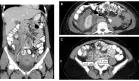

La extensión de la evaluación con tomografía de abdomen y pelvis demostró linfadenopatías retroperitoneales e ilíacas. El estudio PET-TC confirmó la naturaleza hipermetabólica de las adenopatías, con SUV máximo de 18.7 en las lesiones más activas, compatible con proceso linfoproliferativo maligno.

La evaluación de extensión mediante estudios imagenológicos y la ausencia de síntomas B permitieron clasificar el caso como Linfoma de Hodgkin Clásico EBV-positivo, estadio III según clasificación de Ann Arbor. El International Prognostic Score calculado fue 2 puntos (estadio III y anemia), correspondiente a riesgo intermedio.